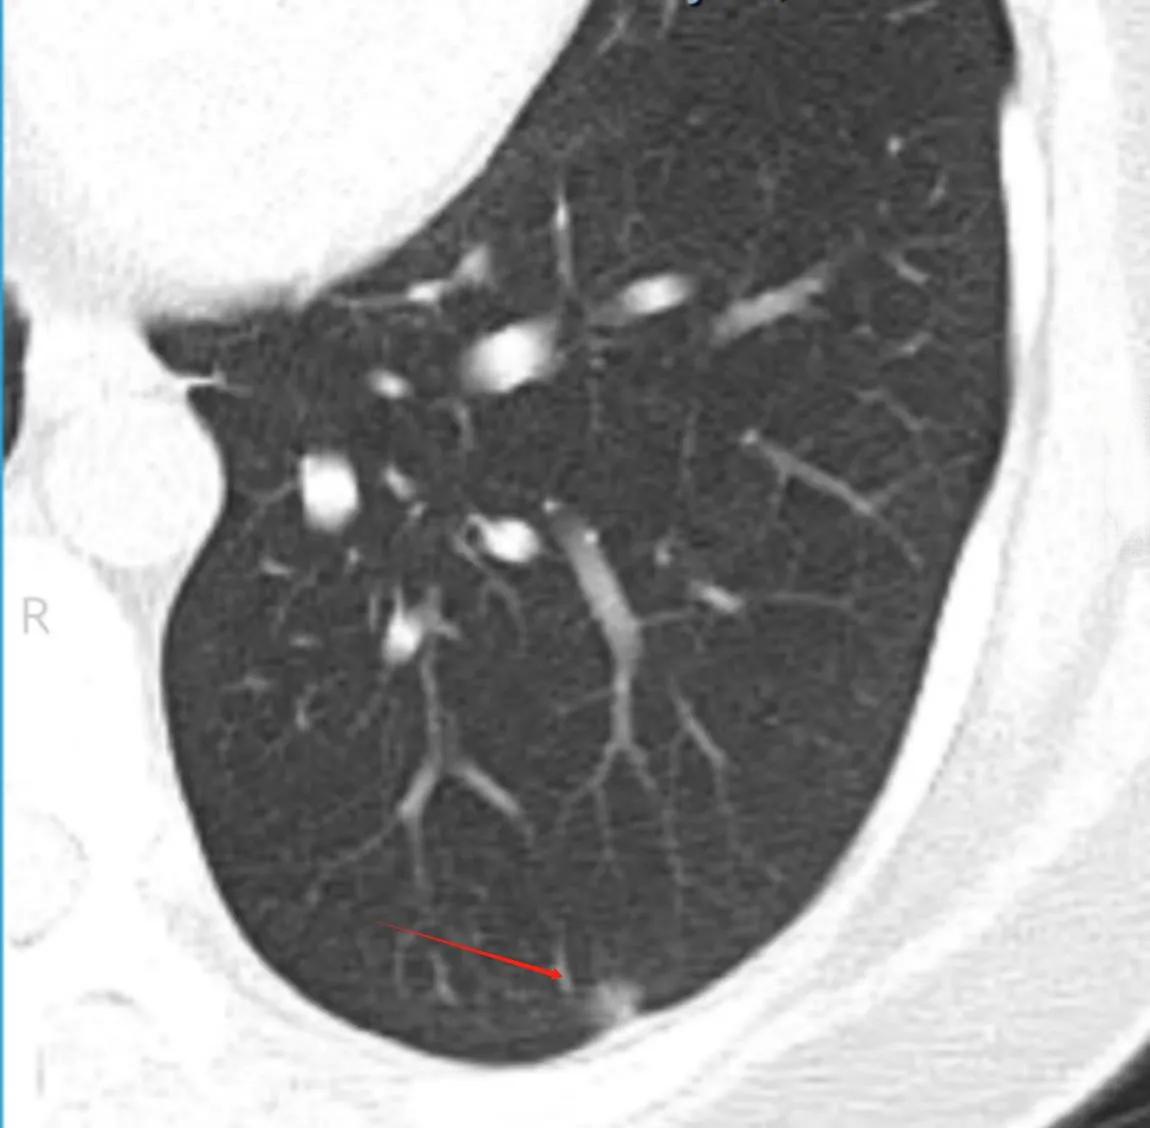

原位癌,顾名思义,是指癌细胞仅在原始发现位置生长,并未侵入周围组织或扩散到其他部位。以肺癌为例,原位癌属于肺癌的最早期阶段,在TNM分期中为“0期”。相比之下,浸润性肺癌则已经突破了基底膜,具有侵袭性和转移性。